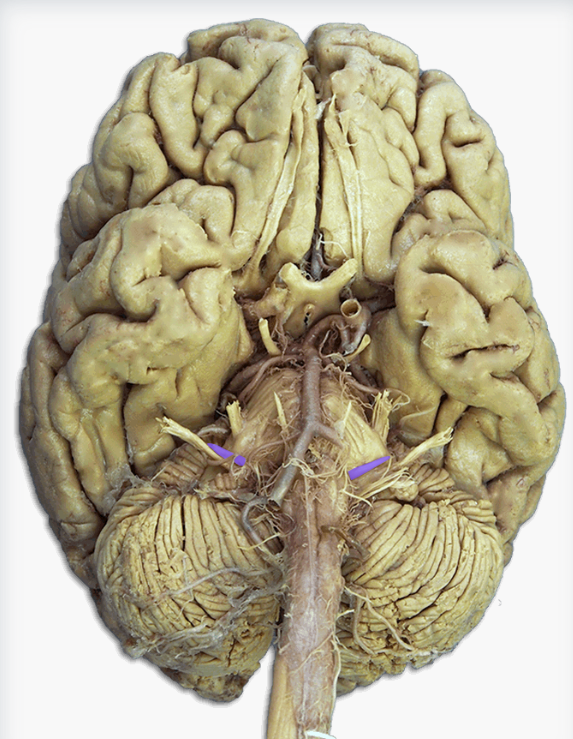

Label this cranial nerve

Olfactory (CN I) nerve

Label this cranial nerve

Optic (CN II) nerve

Label this cranial nerve

Oculomotor (CN III) nerve

Label this cranial nerve

Trochlear (CN IV) nerve

Label this cranial nerve

Trigeminal (CN V) nerve

Label this cranial nerve

Abducens (CN VI) nerve

Label this cranial nerve

Facial (CN VII) nerve

Label this cranial nerve

Vestibulocochlear (VIII) nerve

Label this cranial nerve

Glossopharyngeal (CN IX) nerve

Label this cranial nerve

Vagus (CN X) nerve

Label this cranial nerve

Accessory (CN XI) nerve

Label this cranial nerve

Hypoglossal (CN XII) nerve